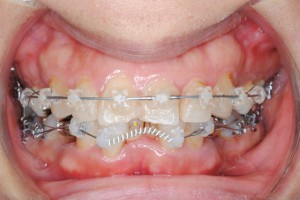

ブラケット装置を装着した状態です。

ワイヤーを装置に装着した状態です。

下あごの歯に装置を装着した後に上顎の歯に装置がぶつかってしまう場合がありますので、装置を削合したりする調整に少しばかり時間を要します。

ワイヤーとブラケット全ての装着に要する時間は、上あごは大体15分くらい、下あごは装置の調整を入れて25分ほどです。